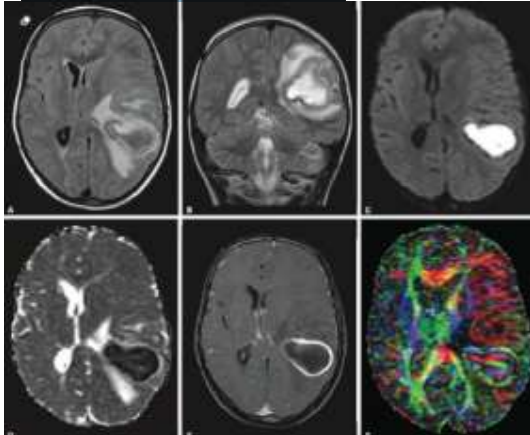

Paciente do sexo feminino, 30 anos, sem comorbidades, imunocompetente, apresentando histórico de cefaleia progressiva e hemiparesia direita. Encaminhada pelo médico assistente para realização de exame de imagem, que segue abaixo.

Baseado na imagem acima, assinale a alternativa correta.